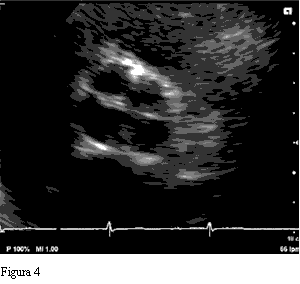

Figura 3 nnnnnnnnnnnnnnnnnnnnnnnnnnnnnnnnnnnnFigura 4

Se presentan las imágenes ecocardiográficas de un hombre de 75 años, tratado por hipertensión arterial, sin síntomas cardiovasculares. El estudio se realizó como rutina para evaluación de su hipertensión.

El ecocardiograma transtorácico mostró un ventrículo izquierdo hipertrófico, con buena función sistólica. La válvula aórtica es cuadricúspide, con cuatro valvas de igual tamaño, y una insuficiencia de grado leve.

Las formas más prevalentes son la tipo B con tres cúspides de igual tamaño y una menor o rudimentaria, y la tipo A, como en nuestro caso, donde las cuatro cúspides presentan el mismo tamaño (8).